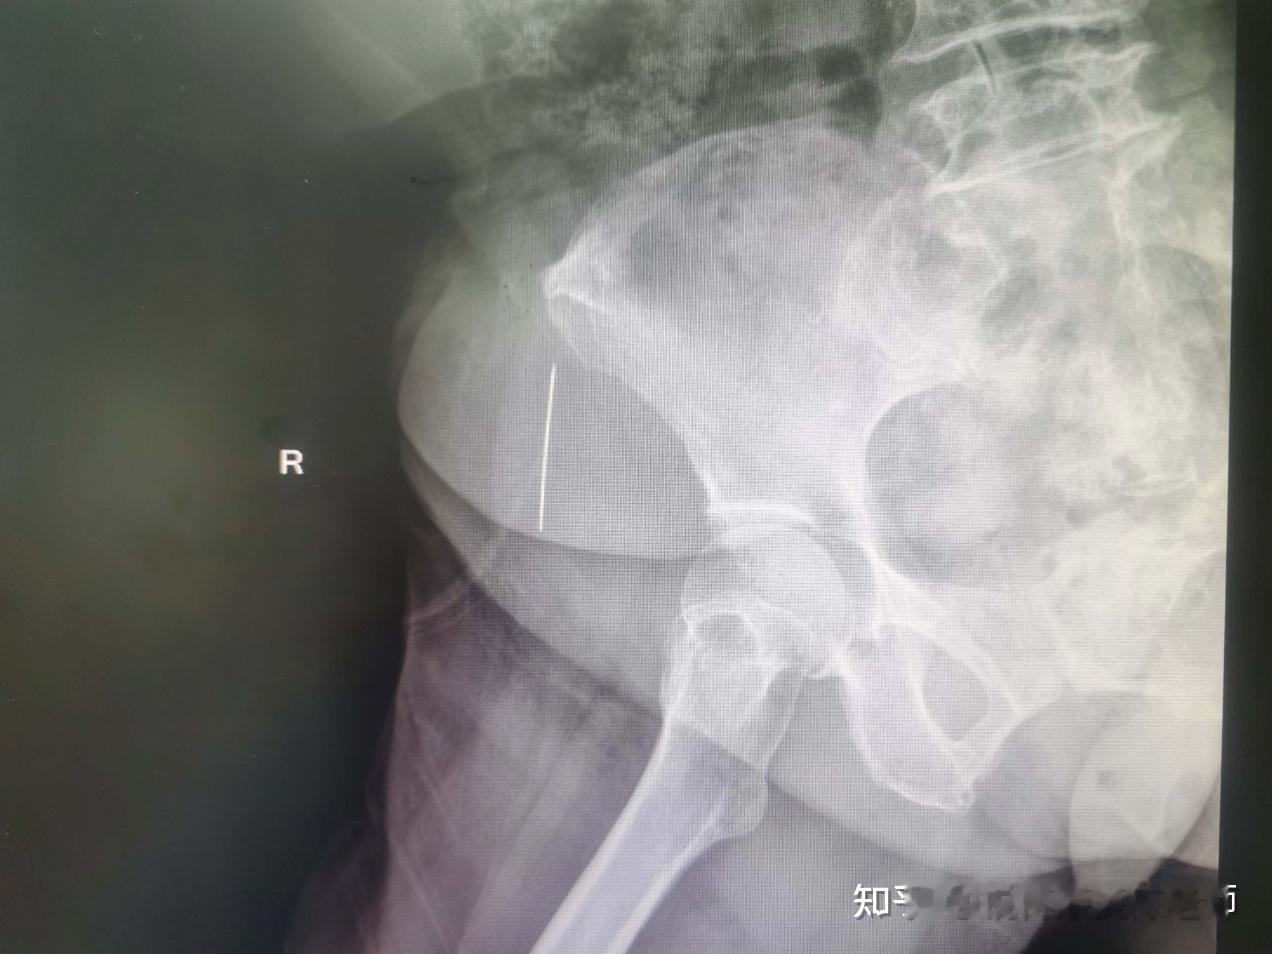

进一步完善腰椎X线检查后发现:大腿内竟然有一枚缝衣针!追问病史,患者这才想起,10天前在家缝被子时弄丢过一根针。